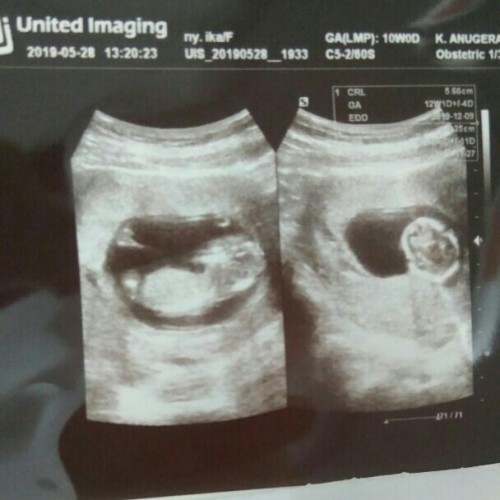

Bund, biasanya kalo USG itu harus udh brpa mnggu sih?

Aku udh 14 mnggu mau USG mlah perawat bidannya nglarang..

Dr 6 minggu jg udh usg, awal kehamilan

Biasanya disaranin pda tm1 tm2 tm3

Dari usia 5w juga udh boleh bun

Aku dari 5 minggu udah usg bund

Saya dari 5 minggu udh usg bun